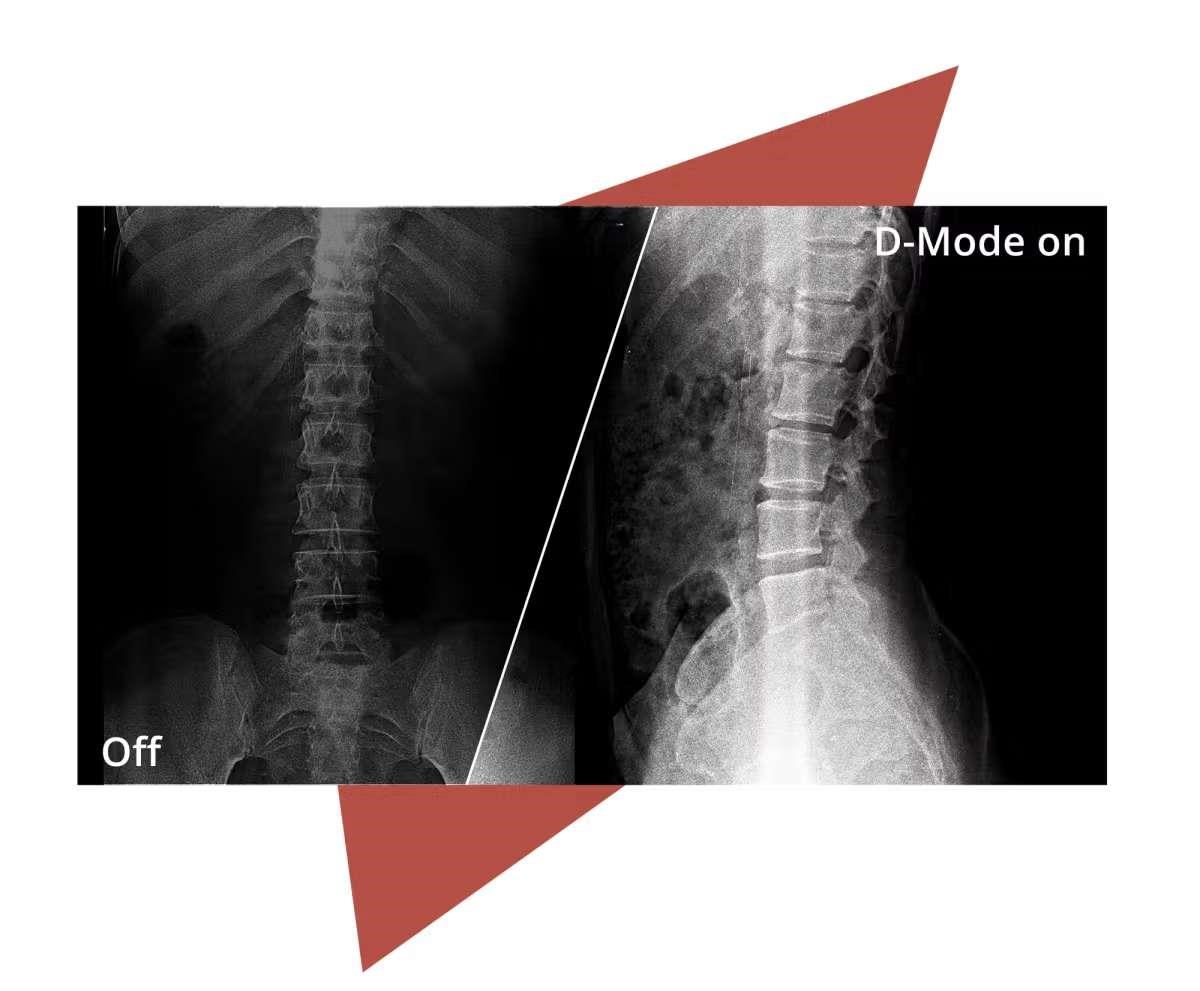

D-Mode

Profesionální monitor s přesností odstínů šedi pro rentgenové snímky.Režim D simuluje standard DICOM Část 14 a poskytuje stabilní a konzistentní výkon v odstínech šedi. Díky tomu lze lékařské snímky, jako jsou rentgeny, zobrazit s vyšší jasností a spolehlivostí v nediagnostických prostředích, jako je školení, konzultace nebo nemocniční administrativa.